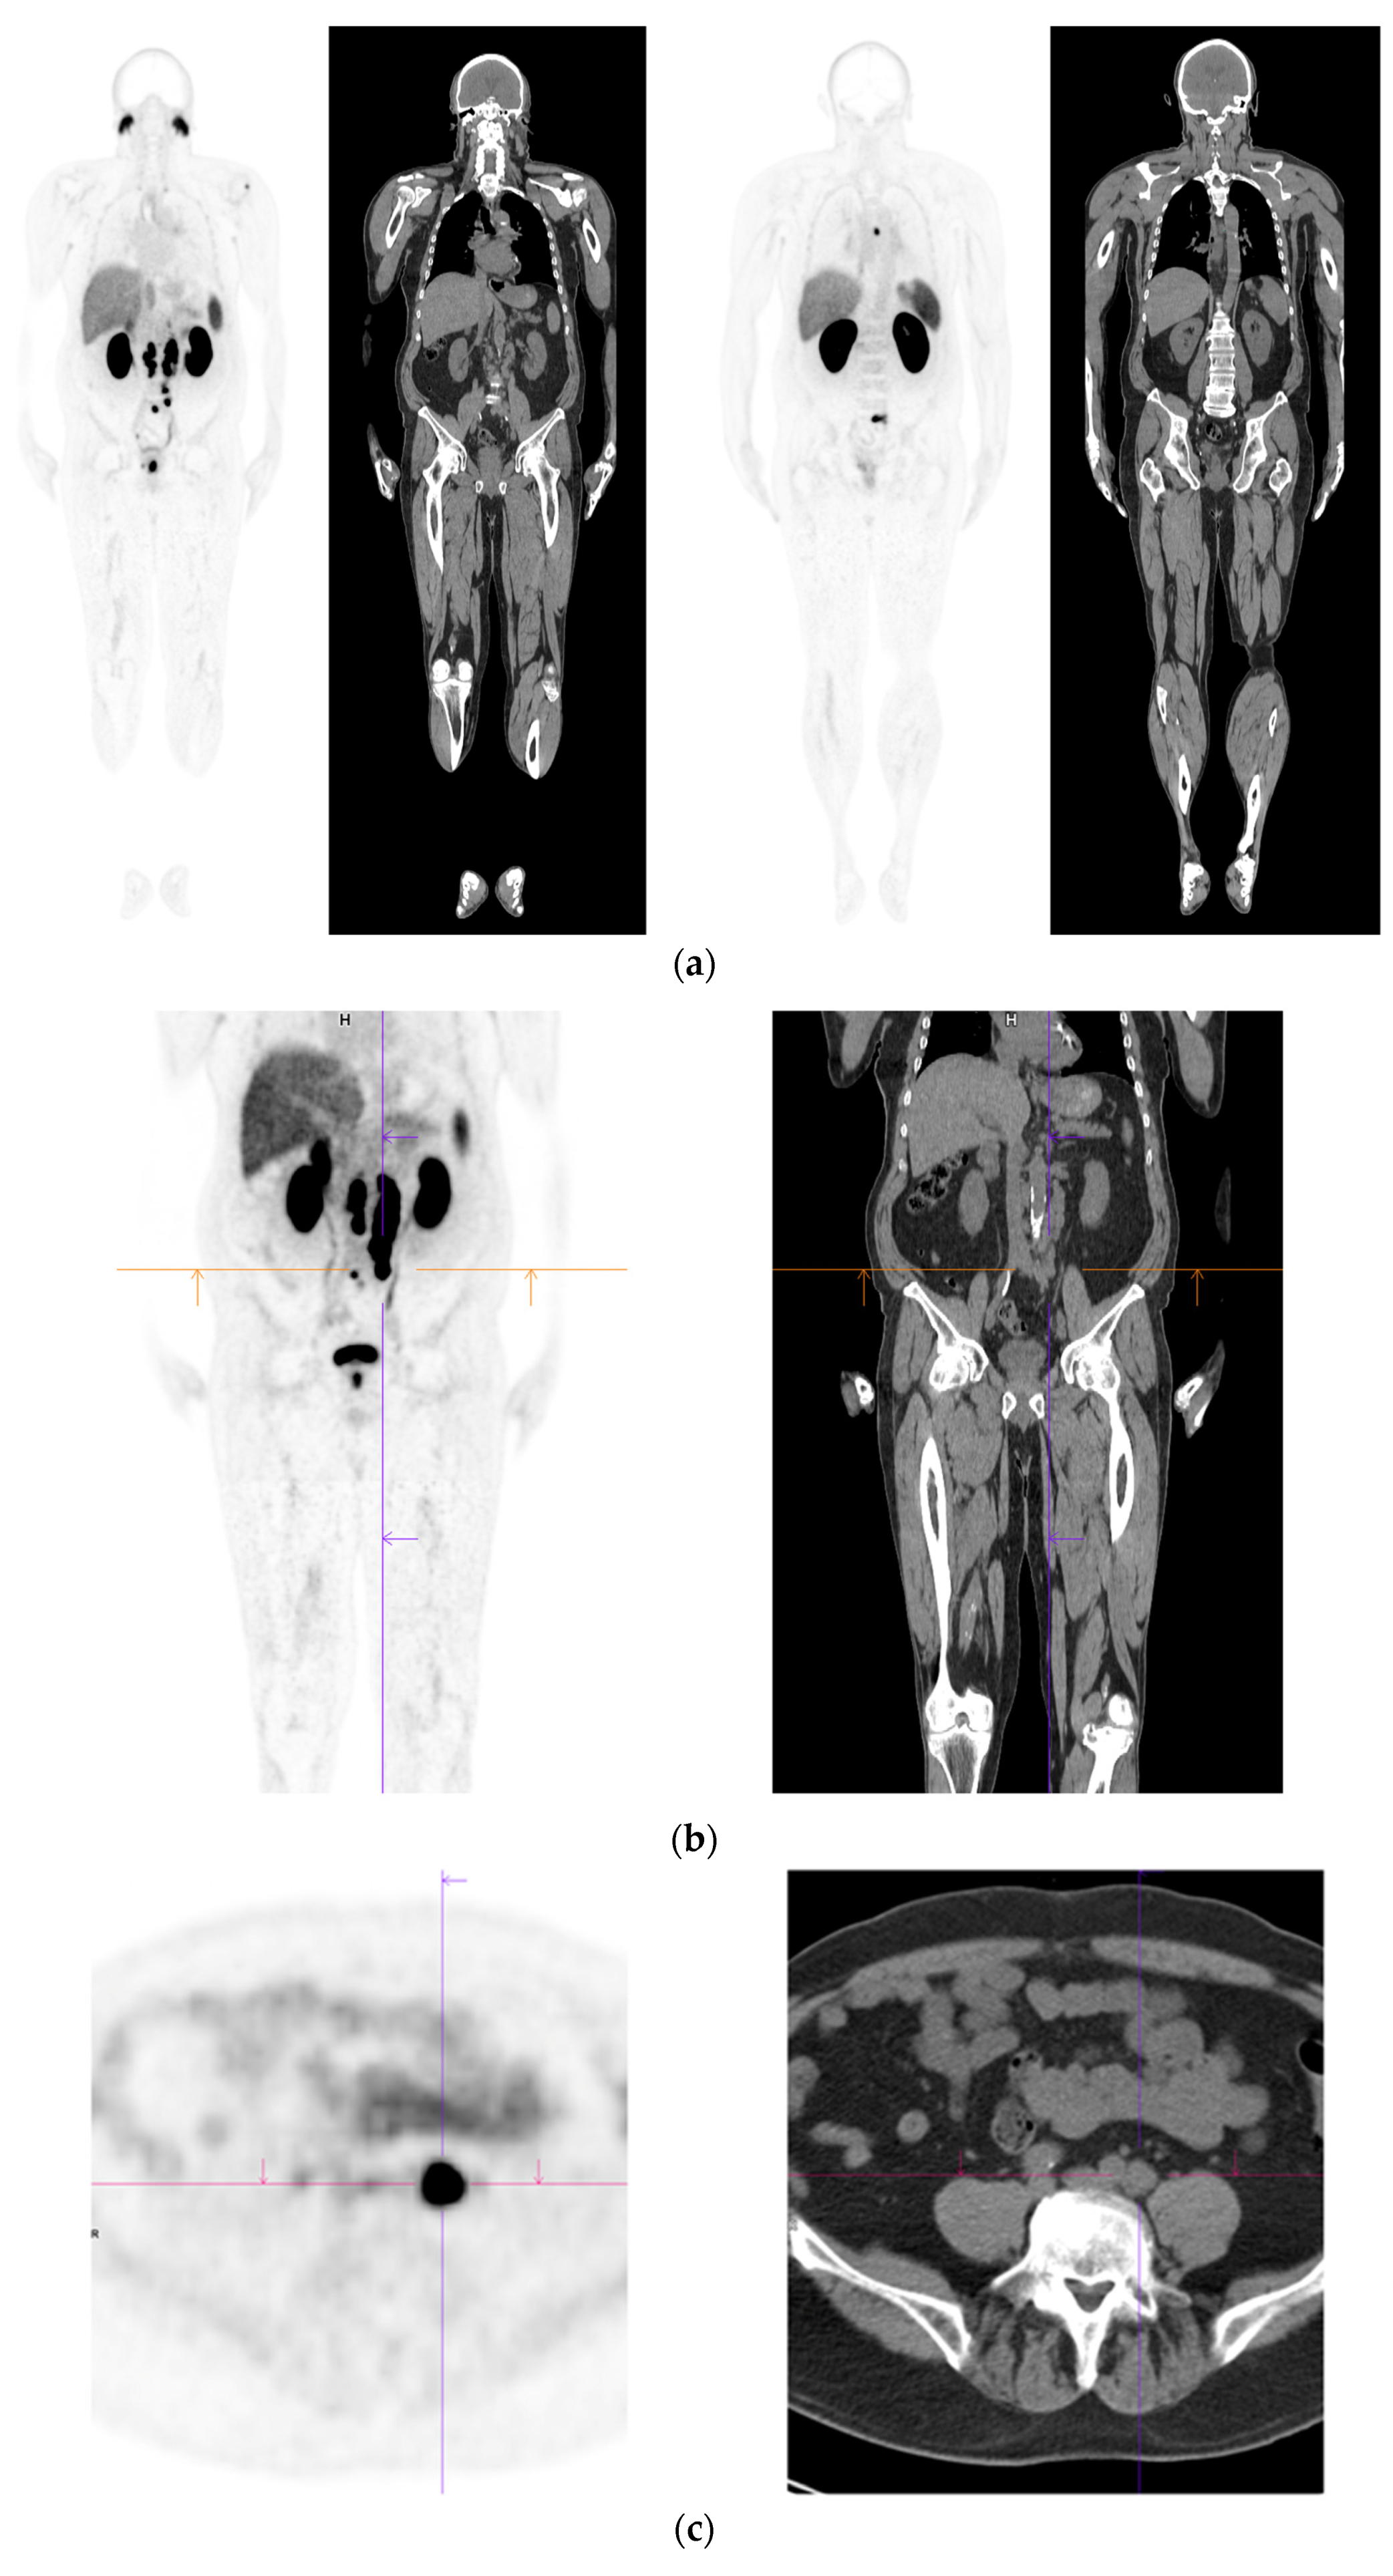

Figure 2.

Primary staging. 70 yr old M; PSA 42; Gleason 4 + 5 = 9; MR scan—PIRADS 6 at right apex; PIRADS 4 at left midzone. PSMA PET-CT: 68Ga-PSMA - 216 MBq; uptake 48 min; BMI = 30.5; Wt 83 Kg. (a): Coronal images—focal uptake midline apex anterior SUV = 26.1 with smaller focus SUV-5.4 right midzone; bulky disease in abdominal nodes; metastasis left humerus; left para-aortic node in thorax; bony metastasis left side of S1. (b,c): enlarged coronal and transaxial images of left common iliac/para-aortic nodal disease and uptake in apex of gland; transaxial images—node measures 14 mm SUV = 40.1; X-hairs show location. (d,e): enlarged coronal and transaxial images of right pelvic nodal that measures 1.4 mm SUV = 5.1; uptake in right midzone and apex as well as disease in left midzone of gland; X-hairs show location. (f,g): enlarged coronal images of para-aortic/para-oesophageal nodal disease in mediastinum; node measures 5.5 mm, SUV = 17.2; X-hairs show location.